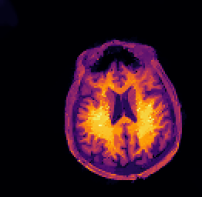

In multi-modality imaging one is often in possession of a specific piece of prior knowledge, namely a side information v𝑣v which is known to have some “common structure” with the true solution u𝑢u of the inverse problem [4]. The literature on this topic is rich with some works as early as the 1990’s so we only list a couple of key papers here. For instance, v𝑣v could be a high-resolution photograph which assists the reconstruction of low-resolution hyperspectral images [5, 6, 7, 8, 9] or an anatomical (MRI or CT) image for the reconstruction of PET images [10, 11, 12, 13, 14, 15, 16, 17], see Figure 2. This strategy has also been used for functional MRI (fMRI) [18], spectral CT [19], electrical impedance tomography (EIT) [20] and multi-contrast MRI [21, 22, 23, 24, 25, 26].

While these approaches can greatly improve the image reconstruction, they all assume that the target solution u𝑢u and the side information v𝑣v are perfectly aligned. If they are badly aligned, most of these methods yield unsatisfactory reconstructions, see Figure 2 for an illustration. In real-world applications such misalignment typically cannot be avoided since frequently the acquisitions of v𝑣v and f𝑓f happen at different times and through different modalities, see e.g. [27].

Figure 1: In many applications two images of different contrast and resolution are acquired. Images courtesy of D. Coomes, P. Markiewicz and J. Schott.

Figure 2: While reconstruction with structural side information (center) can yield very good reconstructions even for noisy data (left), the reconstruction is completely distorted when the side information is misaligned (right).